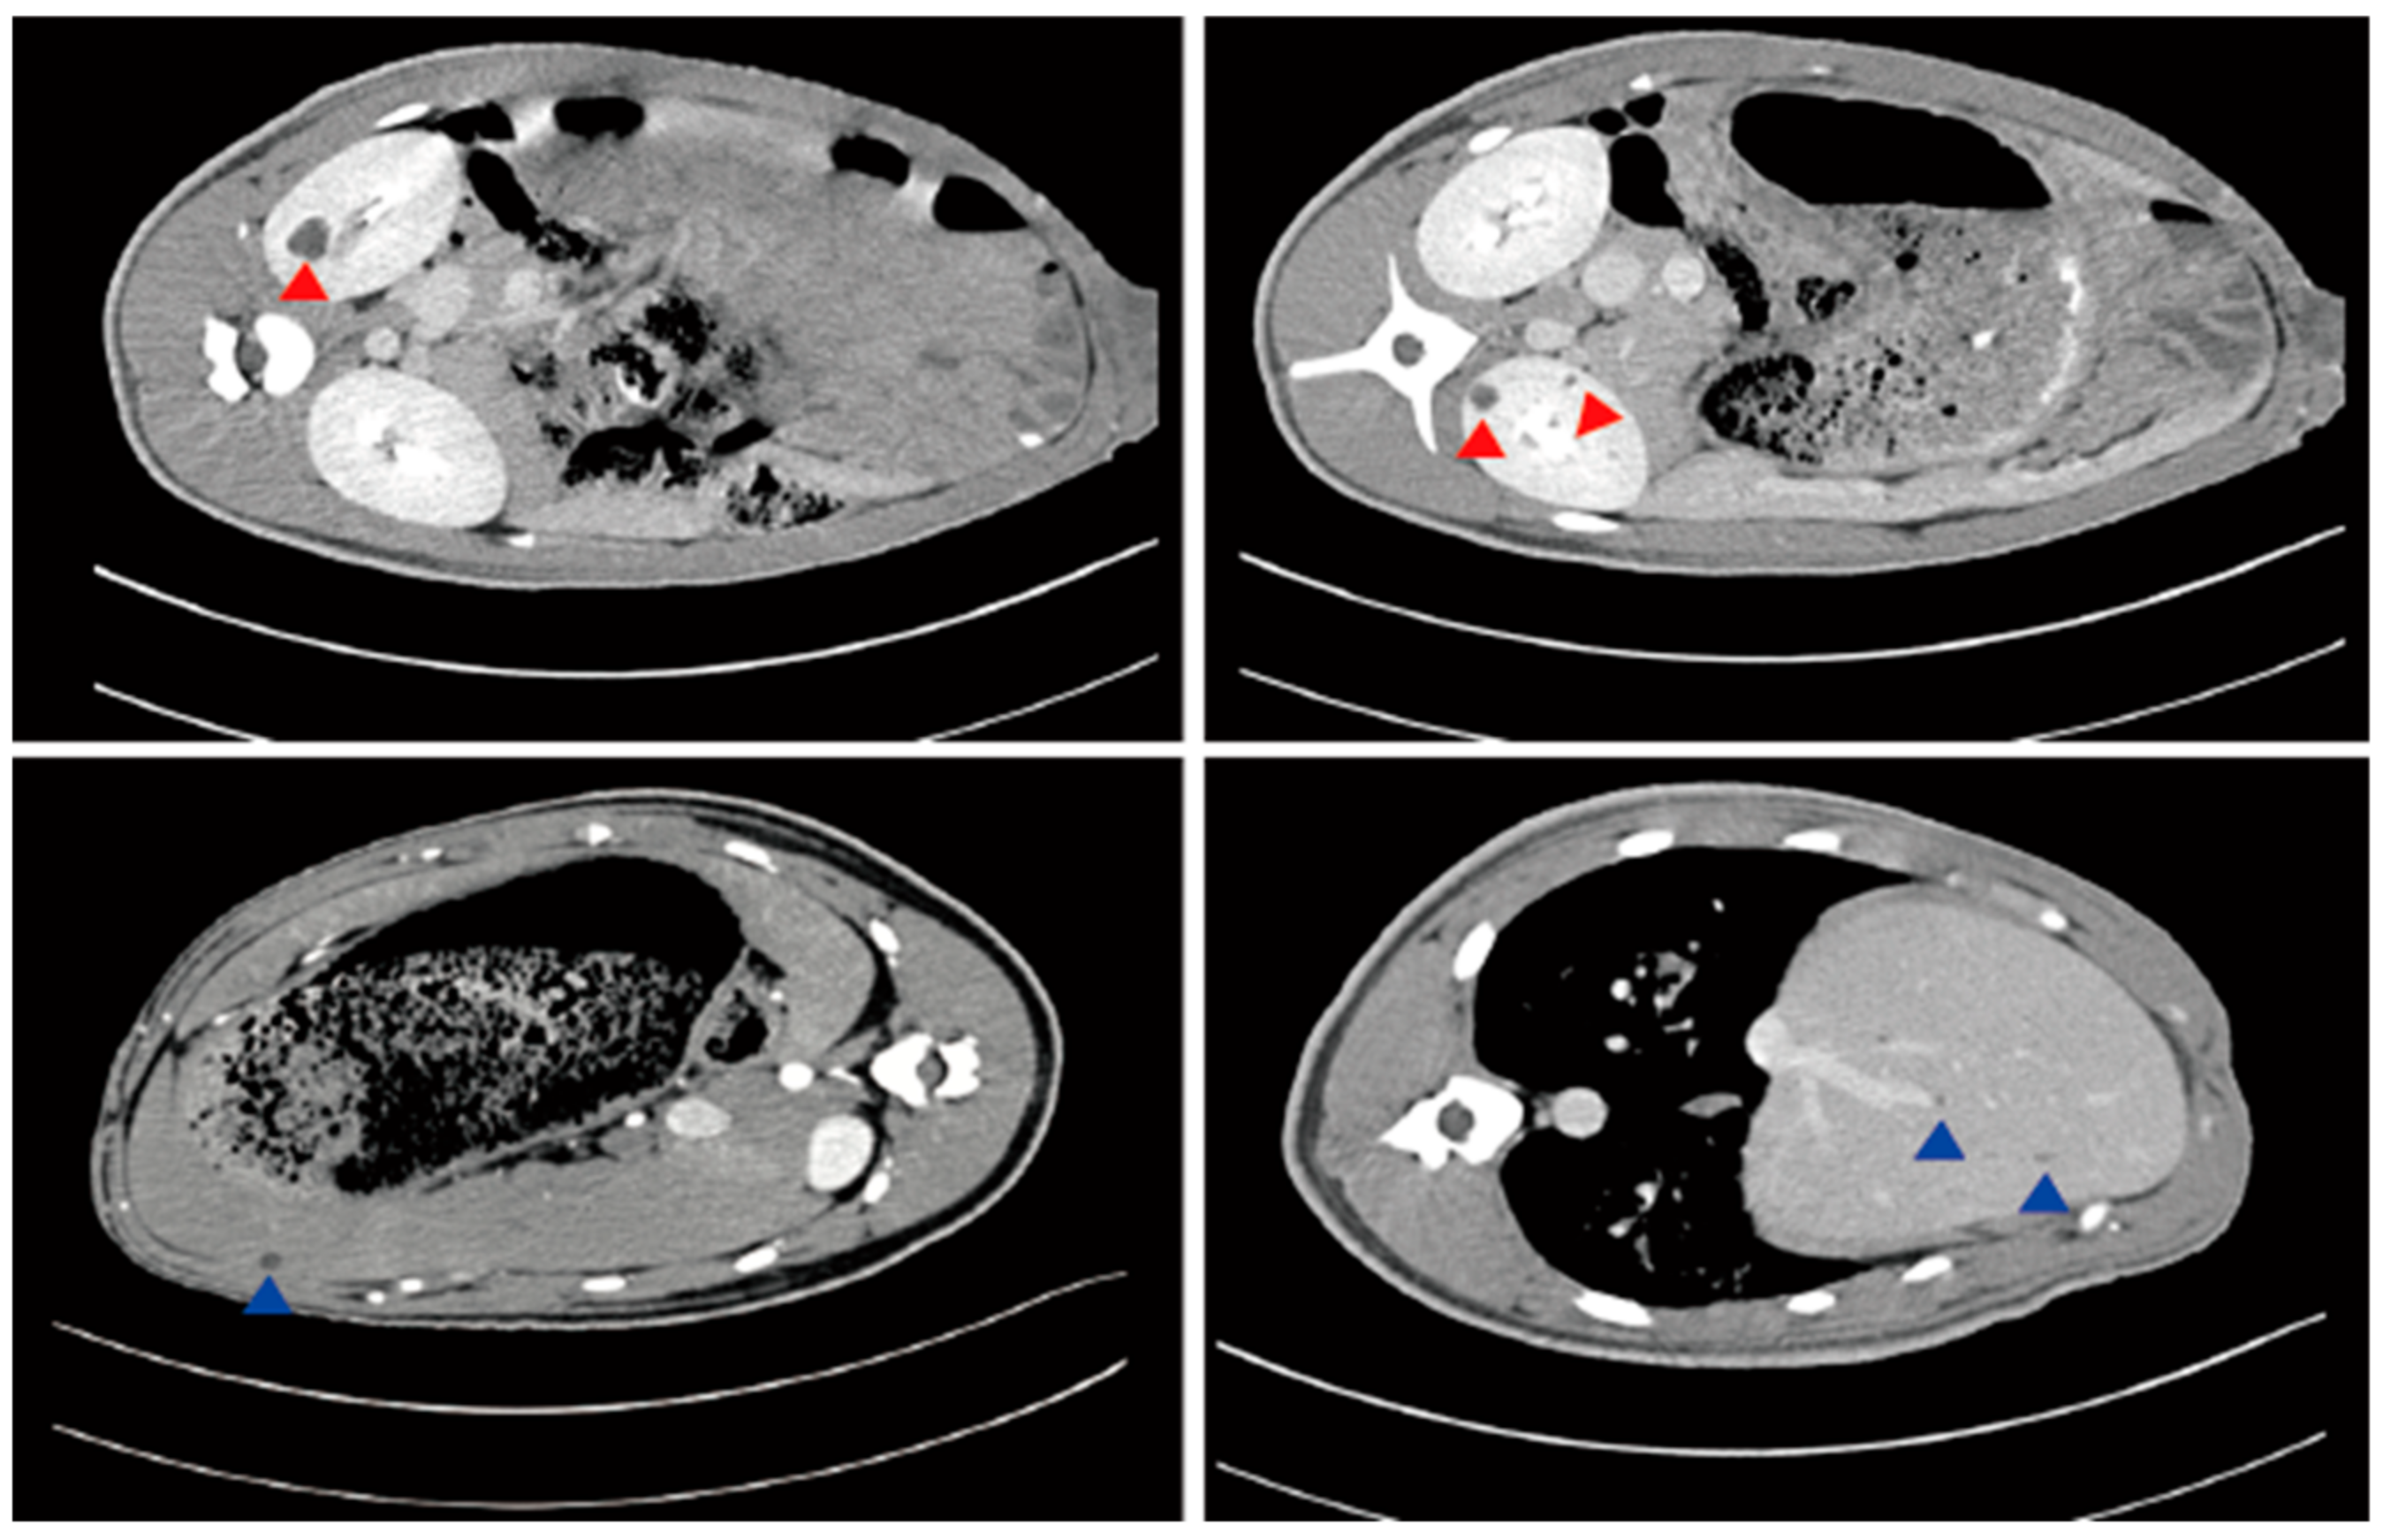

| Imaging studies | Ultrasound, CT scanning, MRI | Ultrasound |